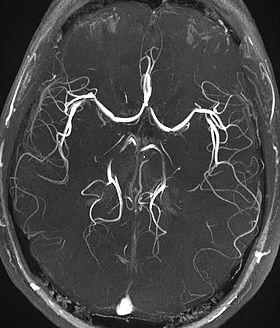

Time-of-flight MRA at the level of the Circle of Willis.

Time-of-flight (TOF) or inflow angiography, uses a short echo time and flow compensation to make flowing blood much brighter than stationary tissue. As flowing blood enters the area being imaged it has seen a limited number of excitation pulses so it is not saturated, this gives it a much higher signal than the saturated stationary tissue. As this method is dependent on flowing blood, areas with slow flow (such as large aneurysms) or flow that is in plane of the image may not be well visualized. This is most commonly used in the head and neck and gives detailed high-resolution images. It is also the most common technique used for routine angiographic evaluation of the intracranial circulation in patients with ischemic stroke.[1]